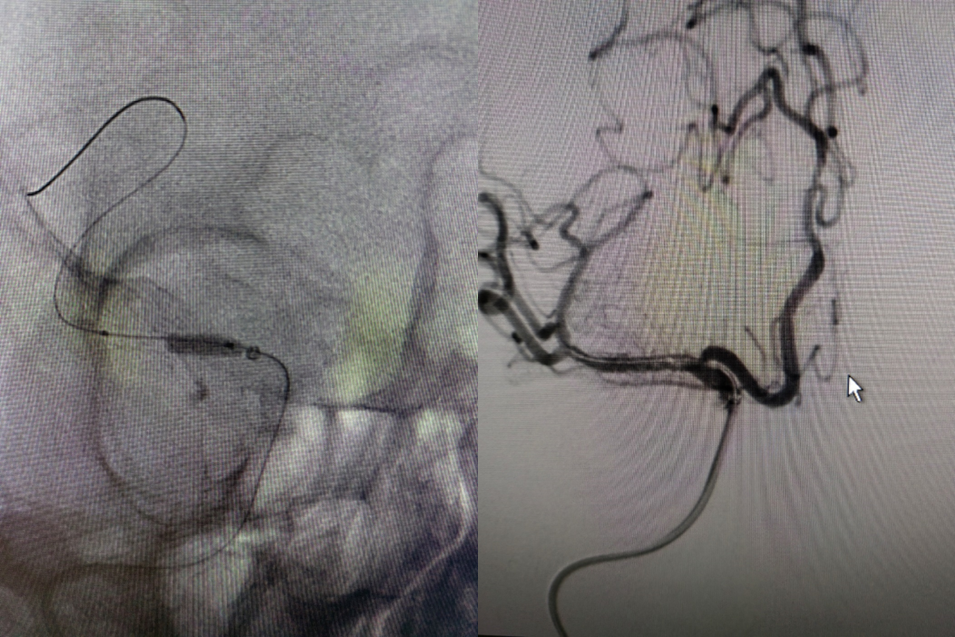

6F-远端通路导管在黑泥鳅导丝的指引下通过闭塞段送至眼动脉段,造影证实闭塞段在海绵窦段,予以ADPAT技术取出少量血栓,仍未开通。

导丝怎么扩【载药时代 球扩天下】NOVA DES®颅内药物洗脱支架在大脑中动脉重度狭窄的应用二例!_https://www.jmylbn.com_新闻资讯_第7张

导丝怎么扩【载药时代 球扩天下】NOVA DES®颅内药物洗脱支架在大脑中动脉重度狭窄的应用二例!_https://www.jmylbn.com_新闻资讯_第8张

通过微导管释放取栓支架,SWIM取栓技术,可见海绵窦段狭窄,前向血流不稳定。

导丝怎么扩【载药时代 球扩天下】NOVA DES®颅内药物洗脱支架在大脑中动脉重度狭窄的应用二例!_https://www.jmylbn.com_新闻资讯_第9张

导丝怎么扩【载药时代 球扩天下】NOVA DES®颅内药物洗脱支架在大脑中动脉重度狭窄的应用二例!_https://www.jmylbn.com_新闻资讯_第10张

利用PTA球囊导管对狭窄处进行扩张,可见狭窄明显改善,但眼动脉段以后闭塞,再次将取栓支架予以取栓,可见斑块逃逸至M1段。